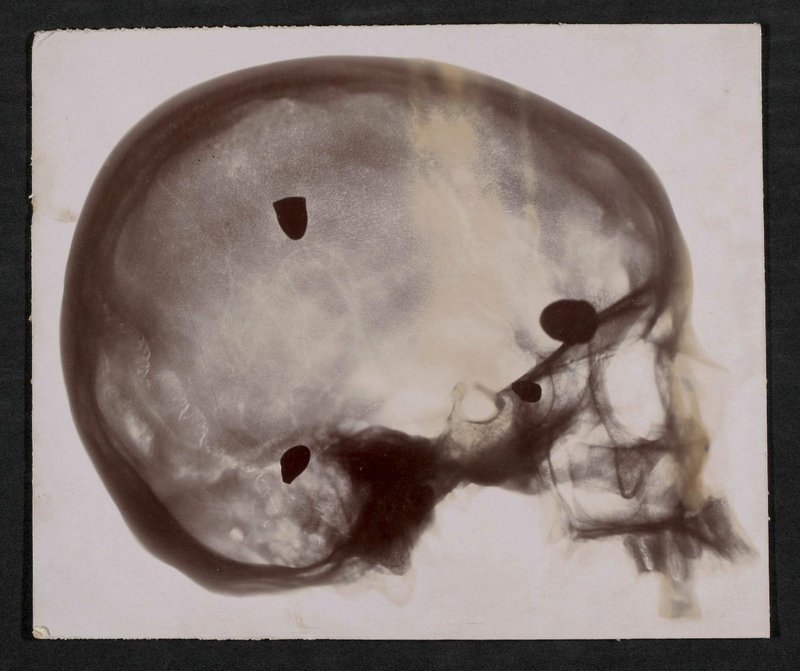

Die Fotografie wurde vermutlich vom Physikalischen Dienst der Fakultät für Medizin und Pharmazie, Toulouse, erstellt. Rückseitig mit handschriftlichen Anmerkungen: Epreuve gouche (=Probe links); bord interne (=innerer Rand); Einl. No. 69 von 24/VII. 1900 Widm. von Dr. C. Marie in Toulouse, Bl. 6; 13070.